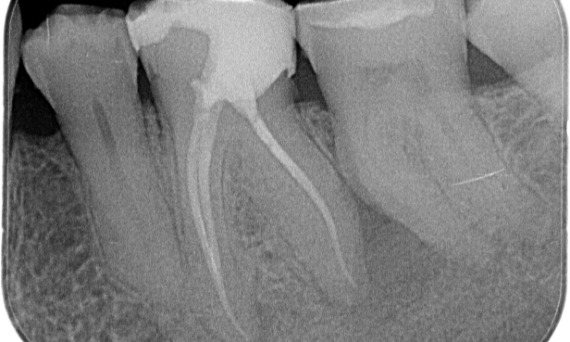

До: Периапикальная рентгенопрозрачность связана, главным образом, с дистальным корнем и потерей твердой пластинки на мезиальном корне.

После: В данном случае была выбрана технология TruNatomy, чтобы обеспечить подход, ориентированный на кариес, и сосредоточиться на сохранении перицервикального дентина, особенно на мезиальной части, где зуб имел в большей степени минимальную реставрацию.